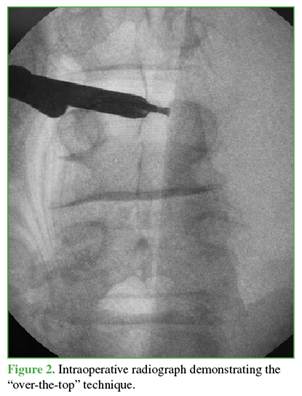

The findings were consistent with a hemorrhagic juxtafacet synovial cyst. Given the acute presentation with progressive motor neurological deficit and severe radicular compression, the patient underwent urgent decompression. The objective was to relieve neural compression, reverse the motor deficit, and allow rapid functional recovery while minimizing invasiveness. A posterior interlaminar uniportal endoscopic decompression was performed using a contralateral (left-sided) approach and the “over-the-top” technique (above the dural sac) to achieve safe and complete cyst resection (Figures 2-5).

The contralateral interlaminar (“over-the-top”) approach was the cornerstone of our success. This technique, recommended for medial lesions and cysts at lower lumbar levels with adequate interlaminar space,9 allowed complete cyst resection from a safe and ergonomic angle while fully preserving the integrity of the symptomatic facet joint capsule. This represents a decisive advantage over a transforaminal approach, which might have been insufficient for a cyst of this size and location, or a direct ipsilateral approach, which could have compromised facet stability on the affected side.10